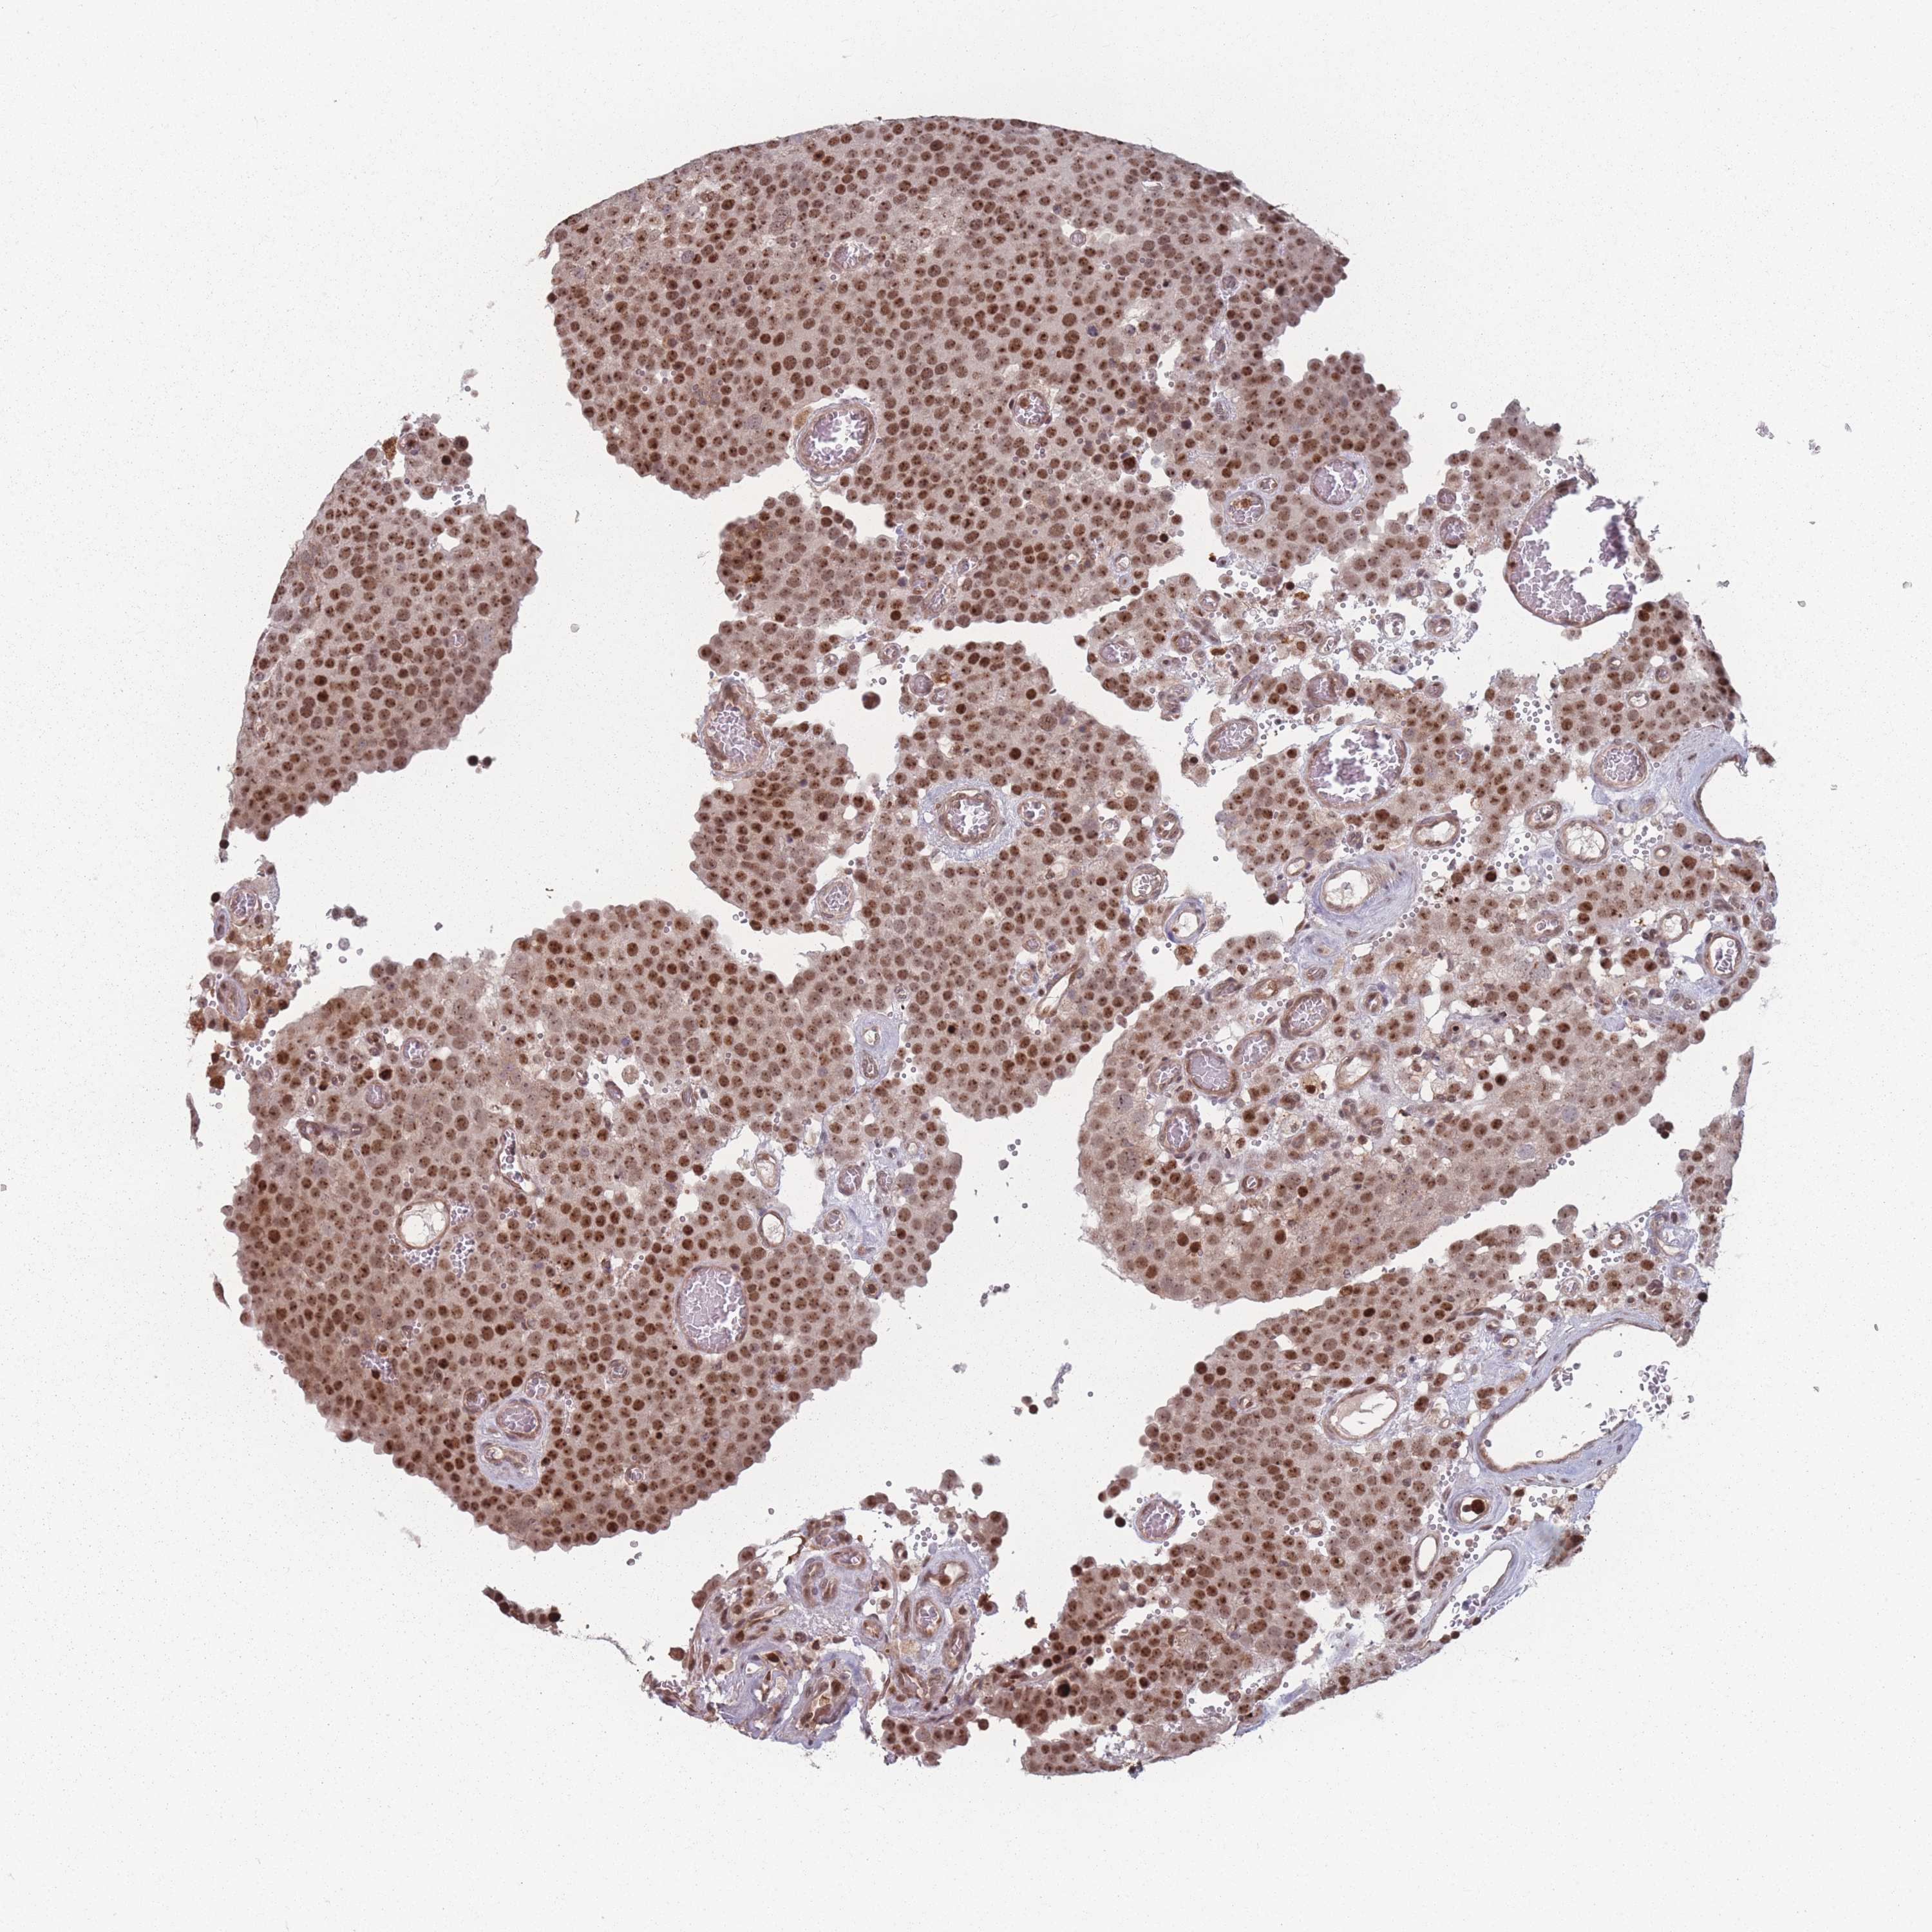

TESTIS CANCER - Protein expressioni

A mouse-over function shows sample information and annotation data. Click on an image to view it in a full screen mode. Samples can be filtered based on level of antibody staining by selecting one or several of the following categories: high, medium, low and not detected. The assay and annotation is described here.

Note that samples used for immunohistochemistry by the Human Protein Atlas do not correspond to samples in the TCGA dataset.

Antibody stainingi

Antibody staining in the annotated cell types in the current human tissue is reported as not detected, low, medium, or high, based on conventional immunohistochemistry profiling in selected tissues. This score is based on the combination of the staining intensity and fraction of stained cells.

Each image is clickable and will lead to virtual microscopy that enables deeper exploration of all samples and also displays staining intensity scores, fraction scores and subcellular localization as well as patient and tissue information for each sample.

Antibody HPA043470

Antibody HPA048143

Staining

High

Medium

Low

Not detected

Intensity

Strong

Moderate

Weak

Negative

Quantity

>75%

75%-25%

<25%

None

Location

Nuclear

Cytoplasmic/membranous

Cytoplasmic/membranous,nuclear

Carcinoma, Embryonal, NOS

Seminoma, NOS